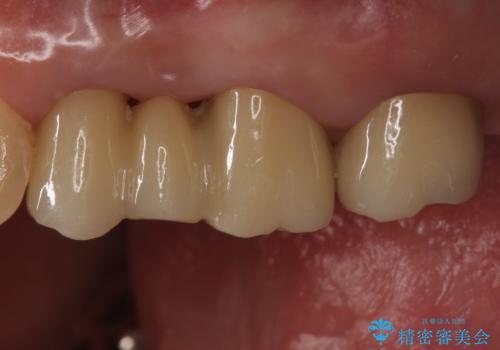

銀歯を白くしたい セラミックブリッジでの治療

- 銀歯を白くしたいとのことで来院。

左上が特に気になるそうであったためまず左上の奥歯から治療をしていここととなりました。

銀歯を除去し、土台の歯にに虫歯がないかを確認します。

今回は目立つ虫歯がなかったため、形を整えて白い被せものを装着しました。

他の銀歯も白くしていきたいとのことで、現在前向きに検討されています。